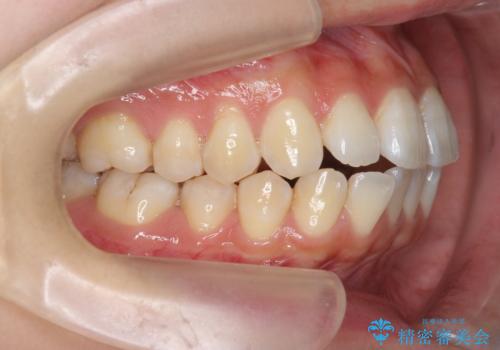

- 前歯の噛み合わせの開きの改善を求めて来院されました。

奥歯はほとんど動かさず(奥歯の噛み合わせはほとんど変えず)前歯のIPR矯正でガタつき前突感(出っ歯感)の改善を計画します。

ほとんど前歯のみの矯正治療であることからトータル14枚のマウスピースで並べるインビザラインライトによる治療を行います。